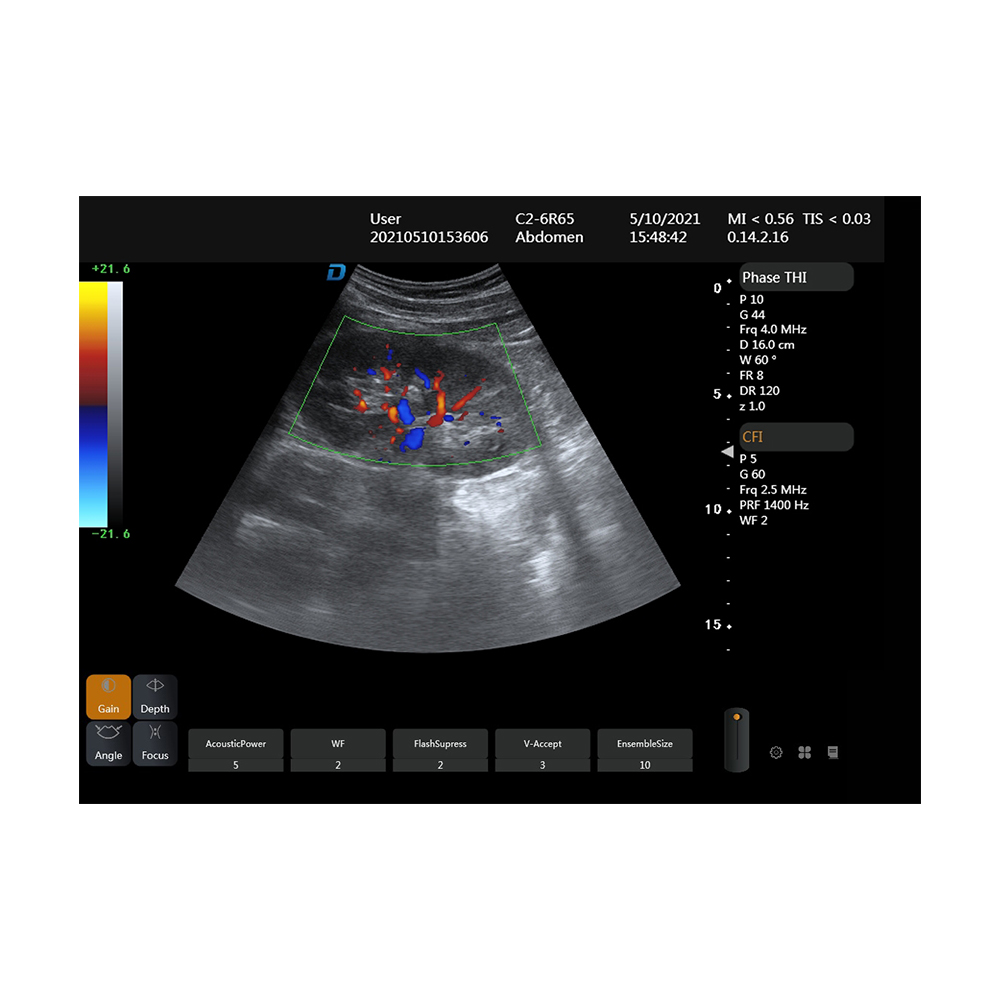

Portable type all digital color Doppler ultrasonic mainframe

B,2B,4B, M, B|C|D,B|C|M,B|C,PW,CFM,CPA

Amain AMDV-P3 Full Digital portable Color Doppler

Ultrasound medicine equipment with High-end Cardiac ultrasound Parameters

Full Digital Color Doppler Ultrasound System

DW-P3 adopts ST-U advanced ultrasonic system platform, and the image is super clear in full time. Overall hardware configuration image power upgrade again, excellent mobile performance, to deal with a variety of complex environment, its birth can enable more medical institutions have cost-effective ultrasound equipment

Imaging mode | Tissue Doppler Imaging |

System | Full digital color doppler ultrasound system |

Product Application

Abdomen, obstetrics, gynecology, heart, urinary system, small organs, superficial, blood vessels, pediatrics, newborns, musculoskeletal

1Tissue Doppler Imaging 2.High resolution medical 15 inch display 3.TGC:8 segment adjustable 4.Real skin rendering 5.Line density:low、middle、high,3 level 6.Frame correlation:0-4,4 level 7.Noise reduction:0-5,5 level